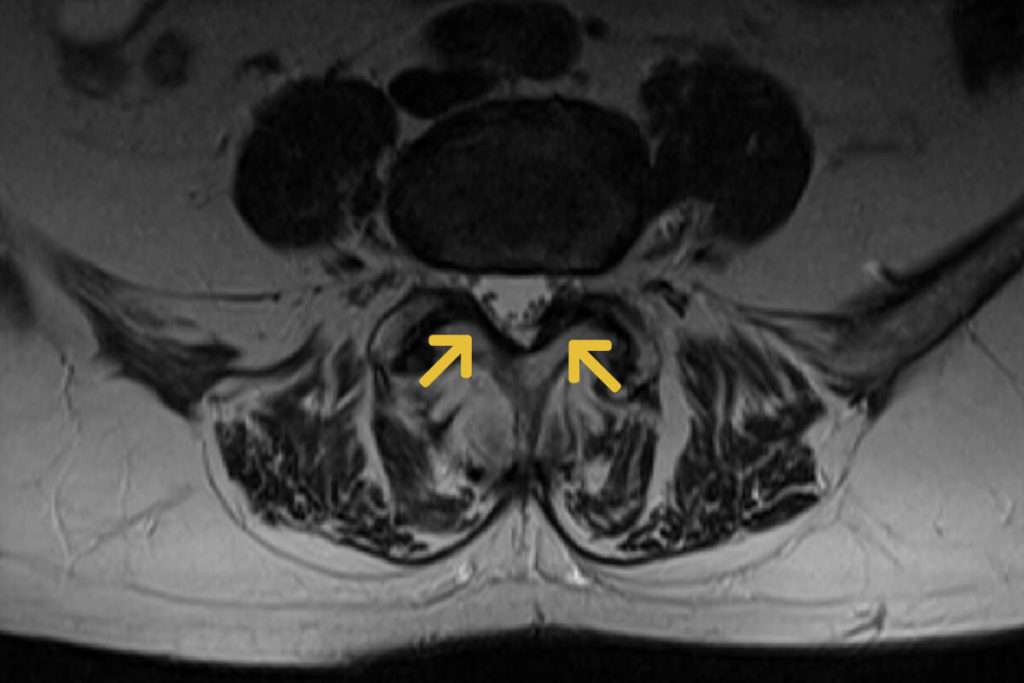

Hier finden sich starke Ähnlichkeiten mit der klassischen Spinalkanalstenose. Durch das „Abrutschen“ zweier Wirbel gegeneinander kommt es zu einem Zusammendrücken des Nervenschlauches beziehungsweise der Nervenwurzeln. Da der Körper dieses Gleiten aufhalten will, reagiert er mit dem Anbau von Knochen und einer Verstärkung der Gelenke und Bänder (Facetten- und Flavumhypertrophie). Hieraus resultiert z. B. auch die häufig schwere Arthrose der kleinen Wirbelgelenke.

Wichtig ist bei der Diagnostik zusätzlich zur MRT die Anfertigung von Röntgenfunktionsaufnahmen, da hierdurch das vermehrte Abrutschen zweier Wirbel beim Rumpfbeugen dokumentiert werden kann.